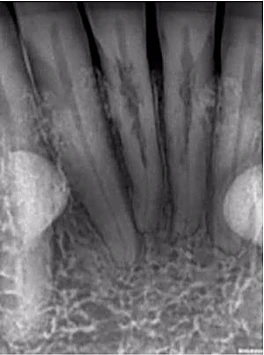

Một phụ nữ 54 tuổi với tiền sử chấn thương tới phòng khám với lý do răng 41 đau và áp xe gây khó khăn khi ăn nhai. Trên XQ 2 chiều thấy tổn thương tiêu ở răng 41 và áp xe ở răng 42 (Hình 1 và 2), rất khó để biết phạm vi nội tiêu theo hướng ngoài – trong. Tổn thương trông có vẻ rộng, nhưng có phá ra phía ngoài hay trong không? May mắn thay, phim chụp từ máy CS 8100 cho thấy nội tiêu chỉ nằm trong phạm vi ống tủy (hình 3 – 5), do đó tôi tự tin rằng điều trị tủy có thể giải quyết vấn đề của bệnh nhân, hai răng này sau đó được đặt Ca(OH)2 rồi trám bít (hình 6 và 7)

Hình 3: Lát cắt ngang trên CBCT

Hình 4: Lát cắt đứng dọc trên CBCT

Hình 5: Lát cắt đứng ngang trên CBCT